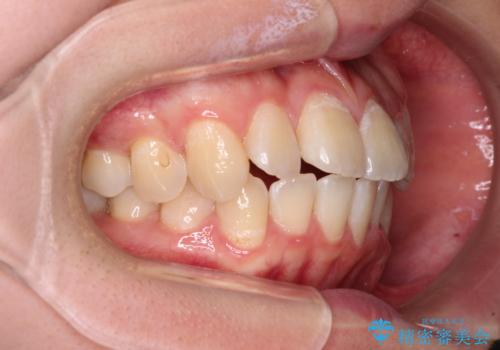

- 前歯のデコボコと八重歯を気にして来院された患者様です。

インビザラインでの治療を希望されていましたが、前歯のクロスバイトや下顎小臼歯の捻転が認められたため、インビザライン単独で治療を行うよりも、ワイヤー装置を併用した方が、治療期間の短縮やトラブル回避できると判断し、ワイヤー装置を併用することとしました。

まずはワイヤー装置により前歯のクロスバイトと下顎小臼歯の捻転を改善し、その後インビザラインにより全体を整える矯正治療を行うこととしました。